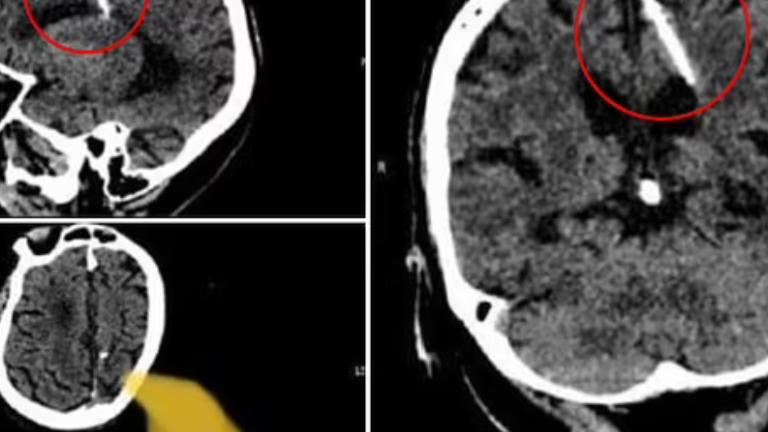

Por medio de una tomografía computarizada, una mujer rusa de 80 años descubrió que ha tenido una aguja de tres centímetros enterrada en su cerebro desde que era bebé.

Los doctores encontraron el objeto cuando la anciana acudió al hospital de Sakhalin, una isla al norte de Japón, para realizar unas revisiones médicas no especificadas. Puesto que nunca experimentó síntomas por el elemento introducido en cuestión, los galenos prefirieron abstenerse de extraerlo por medio de una cirugía.

El departamento de salud de Sakhalin detalló en la aplicación de mensajería Telegram que "la aguja penetró en su lóbulo parietal izquierdo, pero no tuvo el efecto deseado, la niña sobrevivió (...) La salud del paciente no está en peligro; su estado está siendo supervisado por el médico tratante”.

El caso médico se volvió viral por las imágenes compartidas de las tomografías en las que se puede observar la fina varilla metálica entre el cerebro de la paciente. Tras aproximadamente ocho décadas en las que la anciana ha vivido con el objeto sin experimentar un malestar que devenga de este, los expertos pronostican que no enfrentará complicaciones en el futuro.